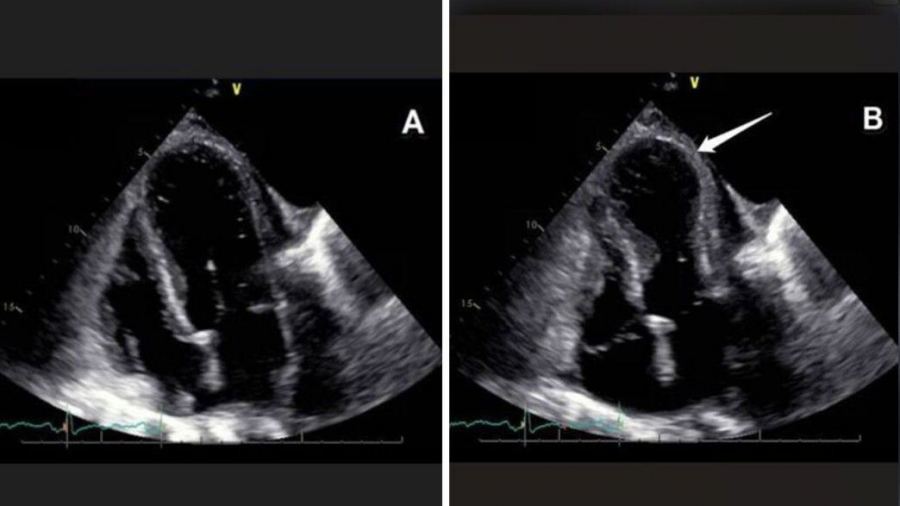

“يصل المريض وهو يعاني من ألم في الصدر، ضيق في التنفس، تغيّرات في تخطيط القلب (تشبه احتشاءً حادًا – STEMI)، وارتفاع في إنزيمات القلب (التروبونين). وفي فحص الإيكو، يظهر نمط مميز يتمثل في توسّع وعدم انقباض قمة القلب (الأبكس)، ما يعطيها شكل ‘بالون’ (Ballooning).”

من اليسار: القلب في حالة ارتخاء، ومن اليمين: القلب في حالة انقباض حيث يظهر بشكل يشبه البالون | تصوير: كلاليت

هكذا يبدو “القلب المكسور”:

في الصورة على اليسار نرى القلب في حالة الارتخاء (الانبساط – دياستول)،

أما في الصورة على اليمين فنرى القلب في حالة الانقباض (الانقباض – سيستول)، حيث ينقبض فقط الجزء القاعدي من القلب بينما يبقى الطرف (القمة) مرتخيًا، ما يمنحه مظهرًا يشبه البالون، دون أن ينقبض هو أيضًا، ولذلك تُسمّى هذه الظاهرة انتفاخ القمة (Apical Ballooning)